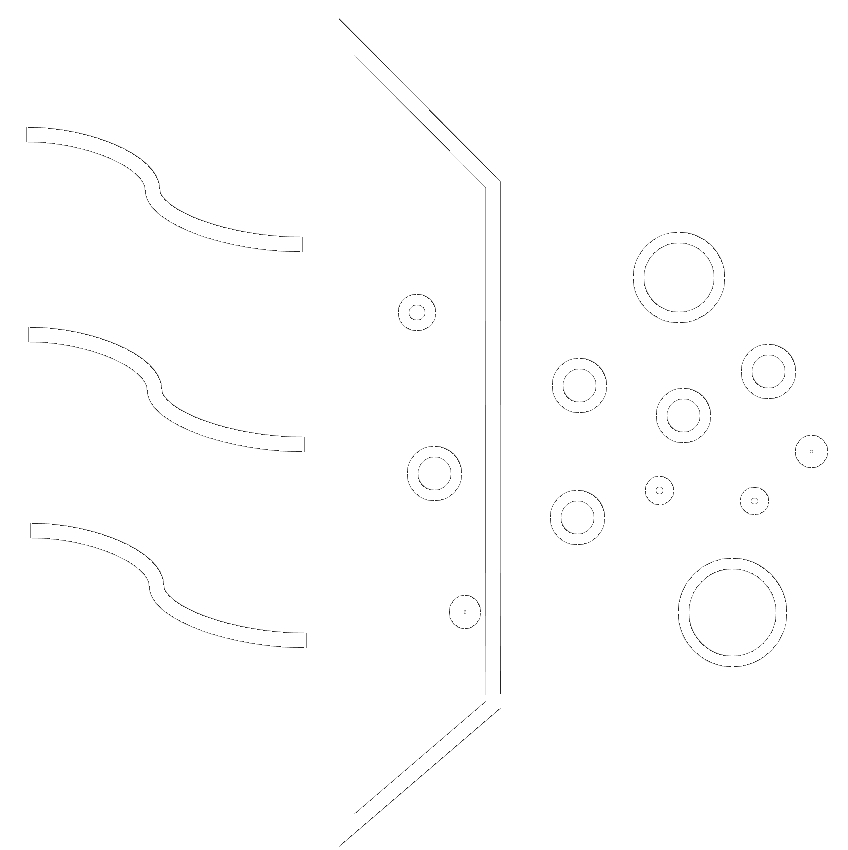

77%

of surgical smoke particles ARE NOT filtered out by standard surgical masks4

ULPA FILTER

IS MORE EFFICIENT THAN HEPA

ULPA filter removes particles as small as 0.1 micron for an efficiency of 99.999%6

A HEPA filter only removes particles as small as 0.3 micron. Most viruses are small than 0.3 micron.6

USE WITH AN ACTIVATED CARBON FILTER

Use a smoke evacuator system that uses a ULPA filter with an activated carbon filter when surgical smoke is anticipated.

When using a medical-surgical vacuum system, place an in-line ULPA filter with an activated carbon filter between the suction wall connector and the suction canister.